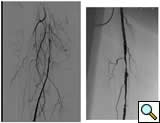

Case 4: A 67-year-old woman with diabetes and tissue loss in the foot secondary to pressure injury with poor healing. Angiogram through an antegrade approach shows a small vessel (average diameter 3 mm) with proximal occlusion and segmental stensoses (Figure 4A). After angioplasty followed by cryoablation, the proximal stenotic areas were treated with 5 mm diameter coronary self-expanding bare stents (Figure 4B). The foot has now healed.

![]() |

| Figure 4A | Figure 4B |